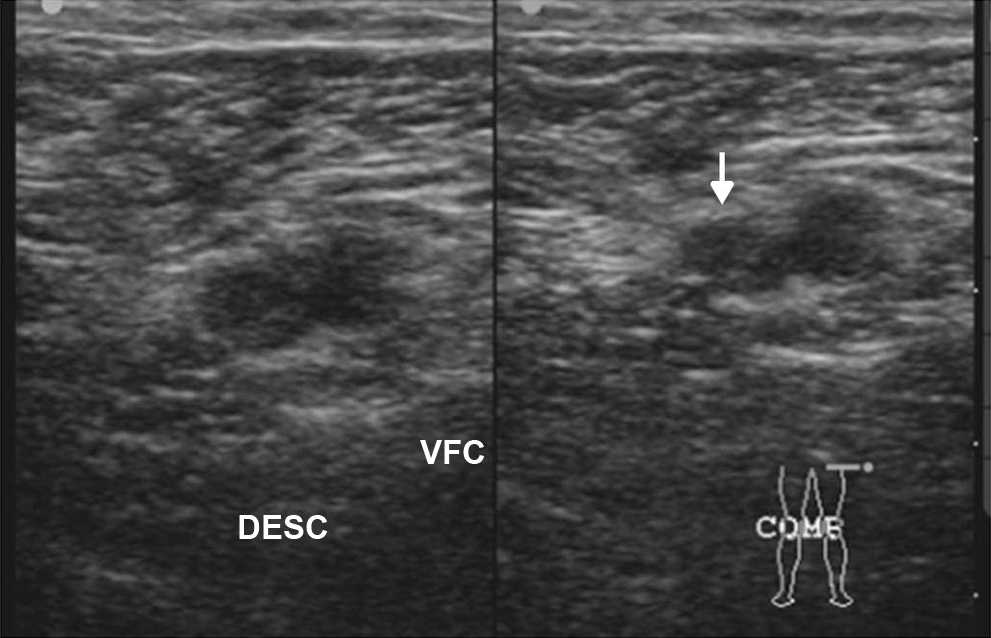

En pacientes con dolor tor??cico agudo y sospecha de embolismo pulmonar, la ecograf??a de miembros inferiores descarta una trombosis venosa profunda (TVP)5. Las maniobras simples de compresi??n-descompresi??n de las grandes venas del miembro inferior permiten confirmar o descartar la TVP en escasos minutos (fig. 21).